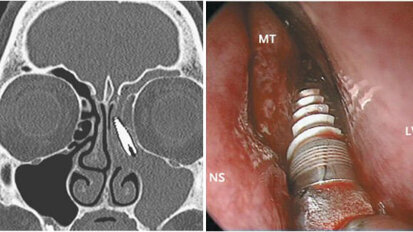

Endo's soms overbodig door vervanger natuurlijk dentine

Bij een pulpaexpositie wordt in de tandheelkunde al snel naar een heftig middel gegrepen: de wortelkanaalbehandeling. Het goede nieuws is dat het in sommige...